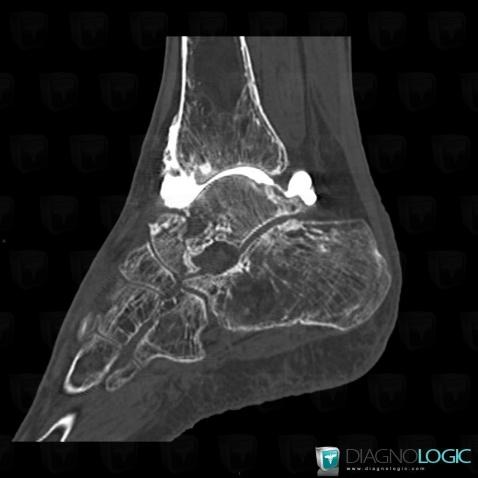

Avascular necrosis, Tibia - Distal part, Calcaneus, CT

Here is the specific information in the key image above:

- Diagnosis Gaucher disease, Location(s) Tibia - Distal part, with gamuts Mulltiple osteolysis

- Diagnosis Avascular necrosis, Location(s) Calcaneus, with gamuts Lucent lesion in foot, Osteolytic lesion of calcaneusTibia - Distal part, with gamuts Well-defined osteolysis